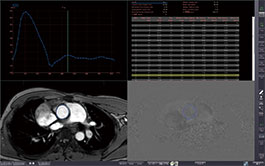

4D TIC

This protocol allows time intensity curves to be generated from one or more ROIs placed anywhere within a multi-phase contrasted volumetric data set. TICs from multiple ROIs can be viewed simultaneously for comparison.